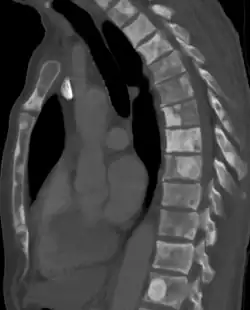

Znacznemu zaawansowaniu miejscowemu zwykle towarzyszą przerzuty odległe[185]. Rak gruczołu krokowego najczęściej daje przerzuty do węzłów chłonnych, kości i płuc[186]. Szerzenie się drogą naczyń chłonnych skutkuje zajęciem węzłów chłonnych[186]. Zajęcie poszczególnych grup węzłów chłonnych odbywa się zgodnie z drenażem limfatycznym narządu[187]. Przerzuty w węzłach chłonnych najpierw stwierdza się w grupach węzłów poniżej rozwidlenia tętnicy biodrowej wspólnej: w węzłach biodrowych wewnętrznych i biodrowych zewnętrznych, następnie dochodzi do zajęcia węzłów biodrowych wspólnych, okołoaortalnych i pachwinowych[186]. Rozsiew drogą krwionośną skutkuje powstaniem przerzutów odległych, które najczęściej pojawiają się w szkielecie osiowym, a rzadziej w płucach, wątrobie i innych narządach[147]. Przerzuty w kościach zwykle mają charakter osteoblastyczny (80%), ale możliwe są zmiany osteoblastyczno-osteolityczne (15%) i osteolityczne (5%)[187][185]. Przerzuty kostne często lokalizują się w kręgosłupie, szczególnie w odcinku lędźwiowym i piersiowym, nasadach kości udowych, miednicy, żebrach, mostku i czaszce[185][186][154][187]. Przerzuty do płuc, wątroby i innych narządów występują raczej w późnym przebiegu choroby i dotyczą one odpowiednio 25% i 20% chorych[186][187].